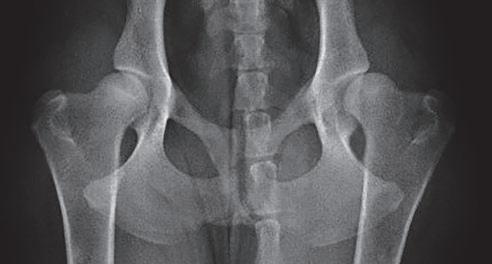

Displasia de cadera (I): etiopatogenia, signos clínicos y pruebas diagnósticas 26